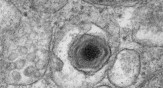

സംസ്ഥാനത്ത് ആഫ്രിക്കന് പന്നിപ്പനി സ്ഥിരീകരിച്ചു... വയനാട് മാനന്തവാടിയിലെ പന്നി ഫാമിലാണ് രോഗം സ്ഥിരീകരിച്ചത്, പ്രതിരോധ നടപടികള് ശക്തമാക്കി മൃഗസംരക്ഷണ വകുപ്പ്

സംസ്ഥാനത്ത് ആഫ്രിക്കന് പന്നിപ്പനി സ്ഥിരീകരിച്ചു... വയനാട് മാനന്തവാടിയിലെ പന്നി ഫാമിലാണ് രോഗം സ്ഥിരീകരിച്ചത്, പ്രതിരോധ നടപടികള് ശക്തമാക്കി മൃഗസംരക്ഷണ വകുപ്പ്. ഇവിടെ കഴിഞ്ഞ ദിവസം ചത്ത പന്നിയുടെ സാമ്പി...

കേരളത്തിൽ വീണ്ടും മങ്കിപോക്സ് ആശങ്ക, രോഗലക്ഷണങ്ങളോടെ സൗദിയിൽ നിന്നെത്തിയ കുട്ടി മെഡിക്കല് കോളേജില് നിരീക്ഷണത്തിൽ കുട്ടിയുമായി സമ്പര്ക്കമുള്ള രണ്ട് പേരും നിരീക്ഷണത്തിൽ

ഇന്ത്യയിൽ സ്ഥരീകരിച്ച രണ്ട് മങ്കിപോക്സ് കേസുകളും കേരളത്തിലാണ് റിപ്പോർട്ട് ചെയ്തിരിക്കുന്നത്. സംസ്ഥാനം മങ്കിപോക്സ് ആശങ്കയിൽ തുടരുമ്പോൾ രോഗലക്ഷണങ്ങളോടെ സൗദി അറേബ്യയില് നിന്നെത്തിയ കുന്ദംകുളം സ്വദേശ...